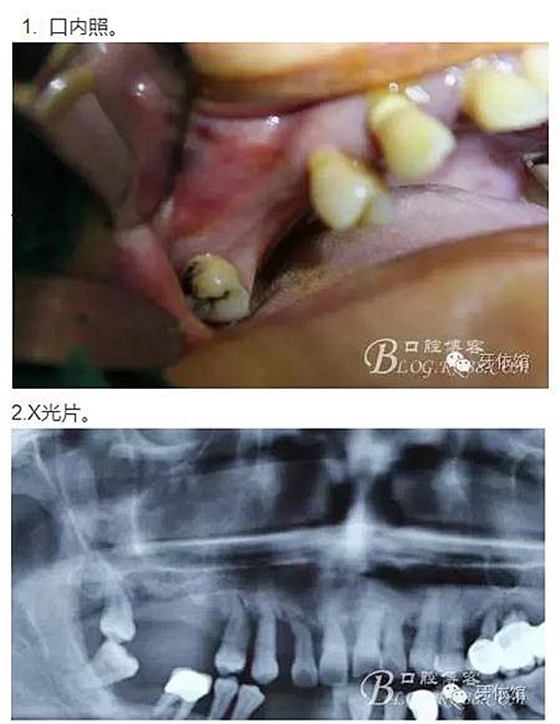

患者女,52歲,全口牙周病,不久前本院大夫剛剛為其做牙周潔治,但余留牙骨喪失嚴(yán)重,穩(wěn)定性差,不知是大夫口才好,還是患者覺悟性高,這種條件也要求種牙。